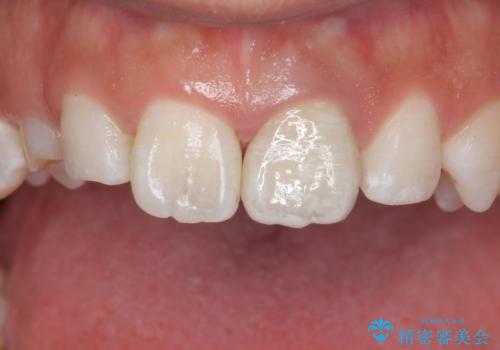

変色した前歯 ジルコニアクラウンでの修復

歯の黒ずみを完全に見えなくすることができ、大変喜んでいただけました。

被せ物を装着する際は、歯の中(根管)から綺麗にすることも重要となります。